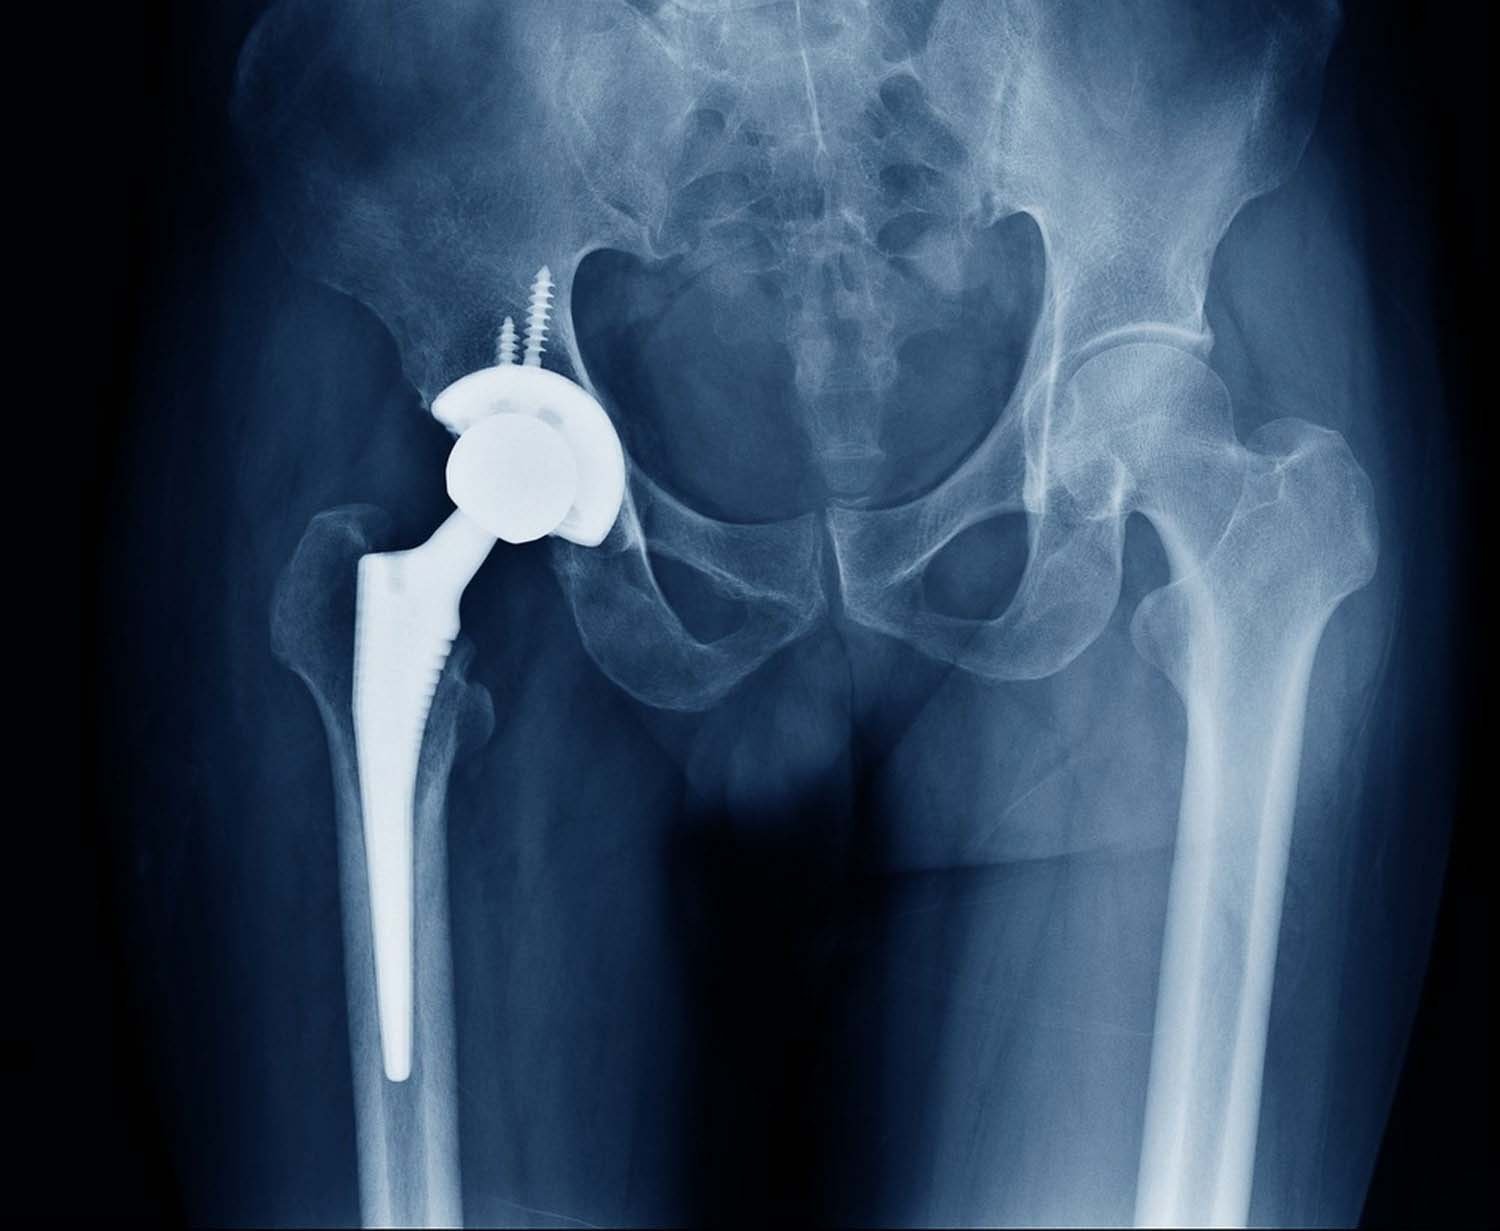

The hip implants are then fitted with or with out the use of special bone cement. The cup is made of metal which sits in the acetabular socket, the stem is made of metal inserted into the femur. The bearing surfaces which include the femoral head (metal or ceramic) and liner (plastic or ceramic), articulate with each other.